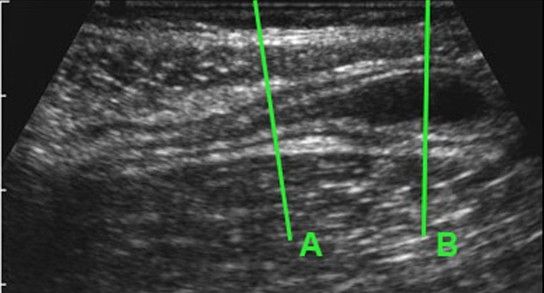

• Υπερηχογράφημα (φώτο με διόγκωση σκωληκοειδούς απόφυσης,  γραμμή Β)